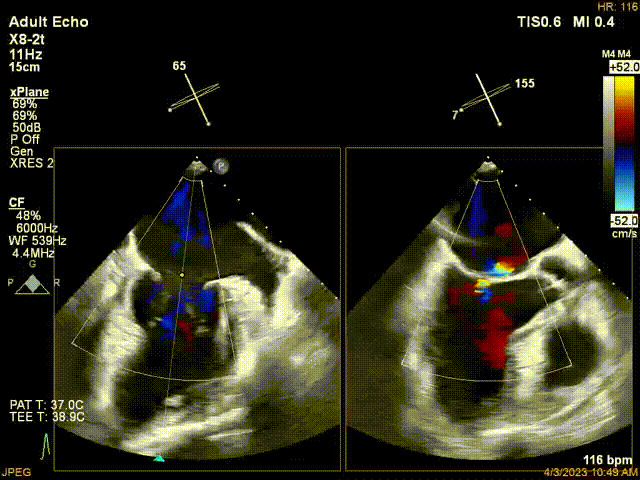

接受治療的是一例器質(zhì)性重度二尖瓣反流(DMR)患者,主訴“反復(fù)活動后胸悶,氣促3年余”。術(shù)前超聲顯示,雙房增大,二尖瓣脫垂伴重度反流,輕度三尖瓣反流,輕度肺高壓,升主動脈增寬。手術(shù)經(jīng)股靜脈-房間隔入路,采用全身麻醉插管,在TEE和DSA引導(dǎo)下完成房間隔穿刺。置入JensClip瓣膜夾系統(tǒng)后,在左房調(diào)整瓣膜夾的位置和軸向,后進入左室,在TEE引導(dǎo)下捕捉二尖瓣前后瓣葉,并關(guān)閉瓣膜夾。經(jīng)TEE反復(fù)確認手術(shù)效果后最終鎖定并釋放瓣膜夾。術(shù)后即刻超聲顯示瓣膜夾位置穩(wěn)定,功能良好,術(shù)前二尖瓣反流4+,術(shù)后0反流,肺靜脈逆流和左房壓都顯著好轉(zhuǎn),手術(shù)圓滿成功(以上數(shù)據(jù)都來源于醫(yī)院的臨床記錄)。術(shù)后患者狀態(tài)良好,目前已安排出院。

術(shù)前超聲提示二尖瓣重度反流